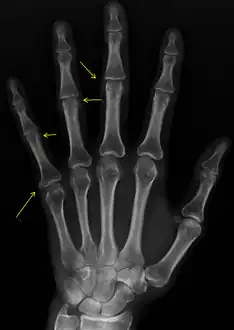

X-rays showing calcinosis in a woman with CREST syndrome -

X-ray of subtle calcifications in CREST syndrome